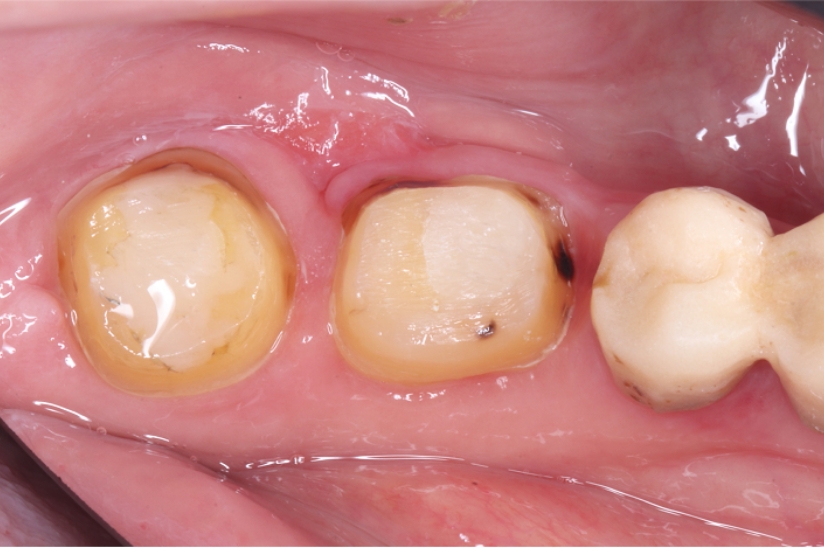

自家歯牙移植で

インプラントと入れ歯を回避した症例

タップで写真の拡大ができます。

Before

After

主訴

インプラントはできないが、入れ歯もしたくない 。

治療内容

自家歯牙移植 / イニシャルトリートメント(大臼歯)レジンコア

治療期間

3ヶ月

治療費用

550,000

治療の

リスク

術後しばらくしてから骨性癒着、外部吸収を起こす可能性があります。